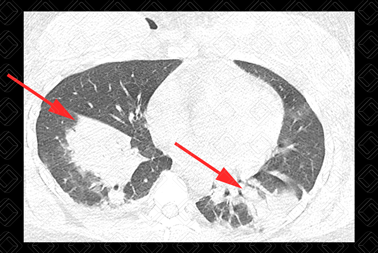

Texto alternativo para a imagem Figura 2. Créditos: Dra. Elazir Mota - Rio de Janeiro/RJ

Descrição das figuras 1, 2 e 3: Tomografia computadorizada de tórax. Consolidações periféricas nos lobos inferiores dos pulmões (setas vermelhas).

• Tomografia computadorizada do tórax: E xame de escolha diante da suspeita clínica. Os achados tomográficos são áreas em vidro fosco e/ou consolidações predominando na periferia do pulmão. Derrame pleural é raro. Esses aspectos de imagem surgem somente após 24-48 horas do quadro (figura 1).